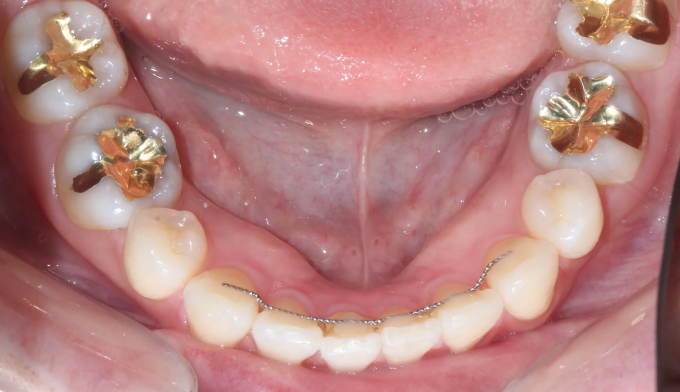

위 유지장치는 모두 제거되어보이고, 아래 유지장치 또한 양 끝이 끊어져서 치아사이가 벌어져 보입니다.

서비스직에서 일하고 있어 치아 안쪽으로 붙이는 설측교정을 원하였고, 9개월만에 교정치료 종료 하였습니다.

유지장치가 떨어지면서 벌어진 치아들과 깊어진 앞니들을 이상적인 위치로 배열시켰습니다.